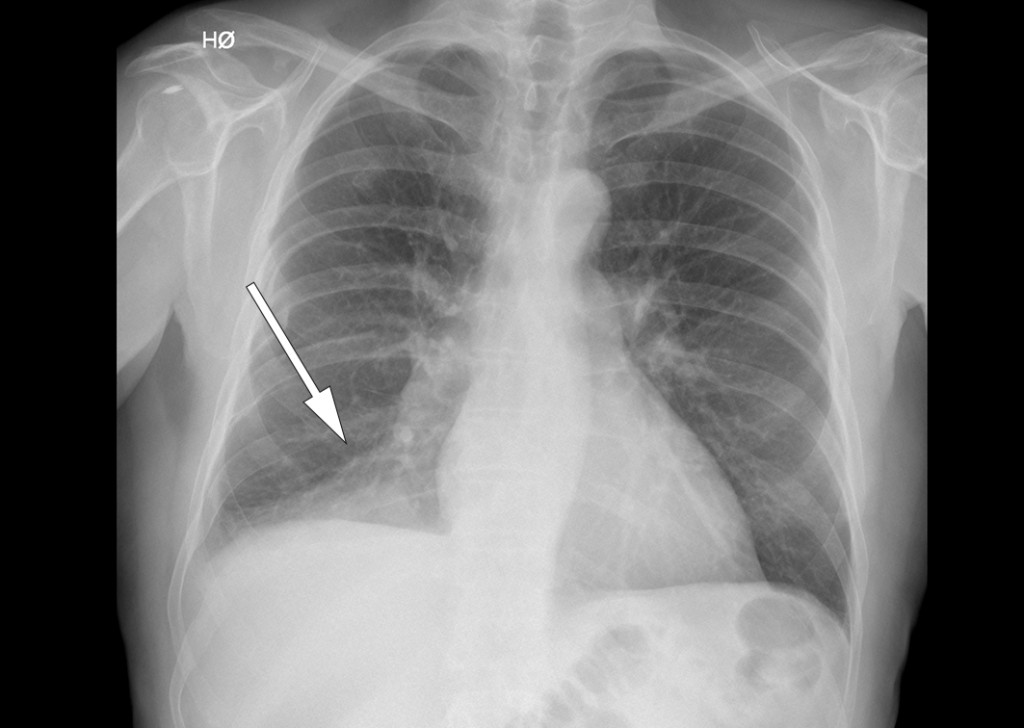

Due to clinical suspicion of pneumonia, a chest x-ray was performed (see x-ray image), which showed a consolidation in the right lower lobe. It gradually emerged that several weeks earlier, the patient had eaten meat soup with vegetables and that during the meal he had become aware that ‘something’ had disappeared down his trachea.